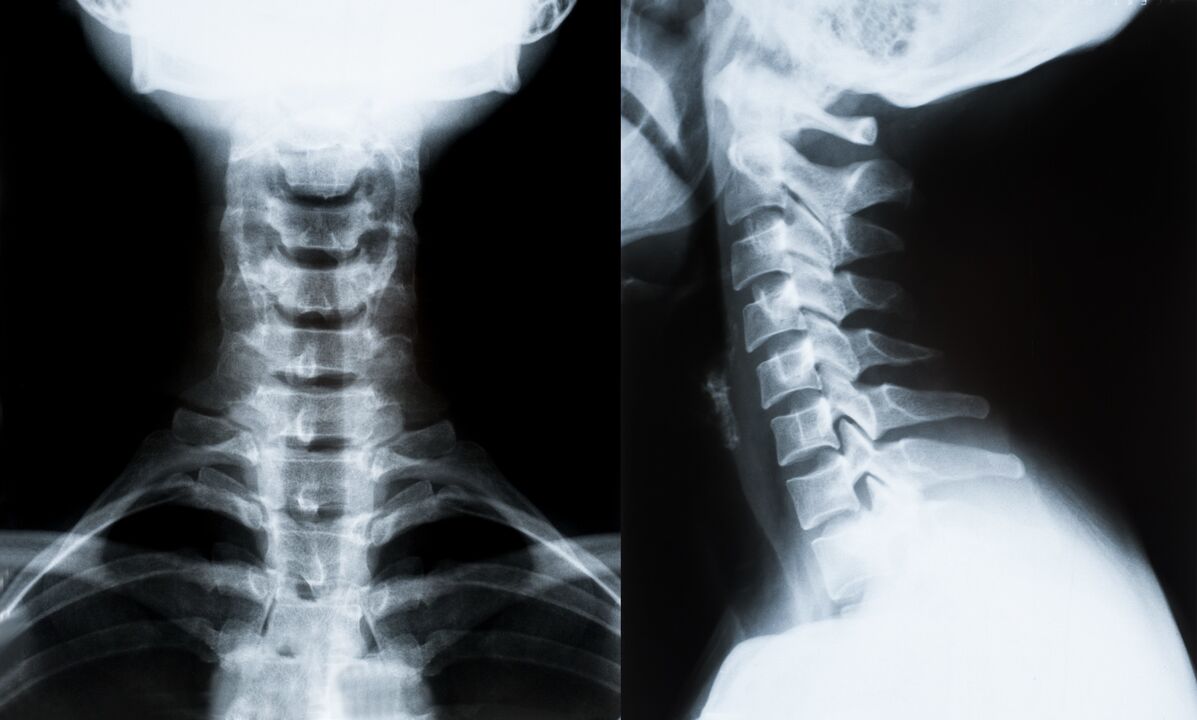

Les principales méthodes de diagnostic et de détermination ultérieure du traitement de l'ostéochondrose de la colonne cervicale :

- Radiographie. La méthode de diagnostic la moins efficace, mais traditionnelle.

- L'imagerie par résonance magnétique est la méthode de diagnostic la plus efficace. Avec ce type d’examen du patient, toutes les structures nécessaires sont visibles.

- Si les changements doivent être mesurés, la tomodensitométrie est utilisée. Détermine la présence de hernies et d'autres choses.

- La dernière méthode est l’échographie duplex. Cette méthode de recherche détermine la vitesse du flux sanguin dans les artères.

Il est impossible de déterminer avec précision une maladie de la colonne vertébrale à la maison.